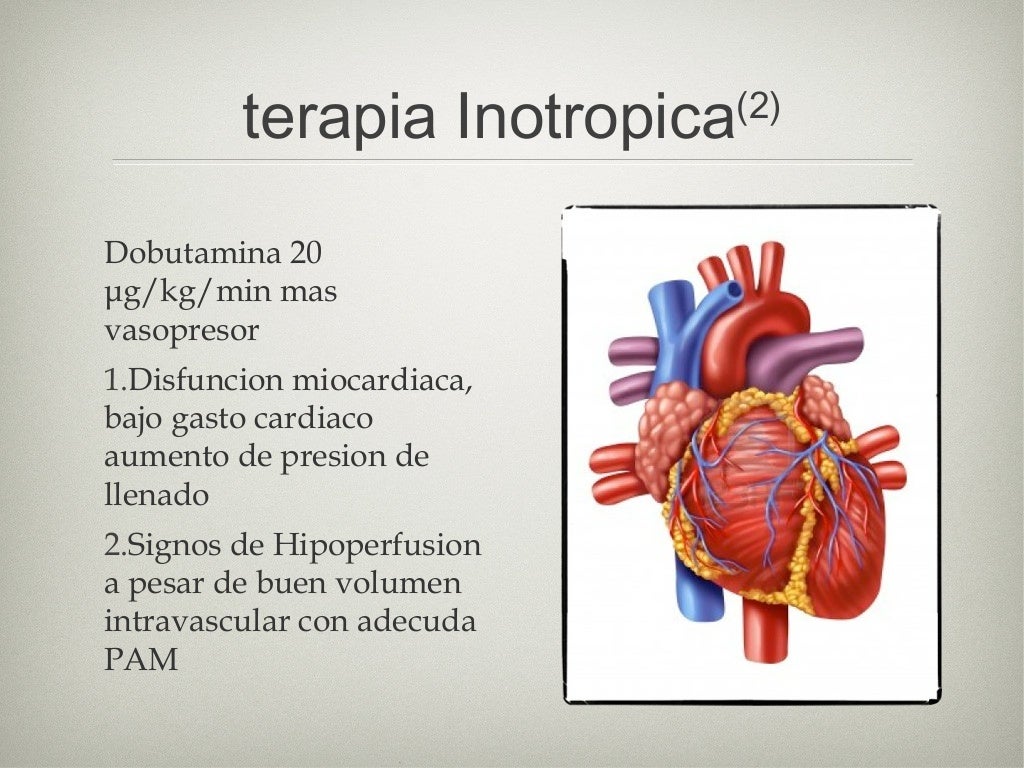

Sepsis abdominal fisiopatología, diagnóstico y tratamiento Medcmc